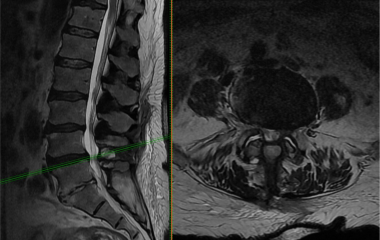

Lumbar laminectomy

Laminectomy is an open surgical procedure that removes the lamina, a thin layer of bone that covers the spinal canal. It is done to relieve pressure from the nerves that causes pain, numbness or weakness.